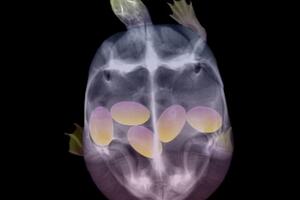

Ovako izgledaju bebe životinja prije nego što se rode